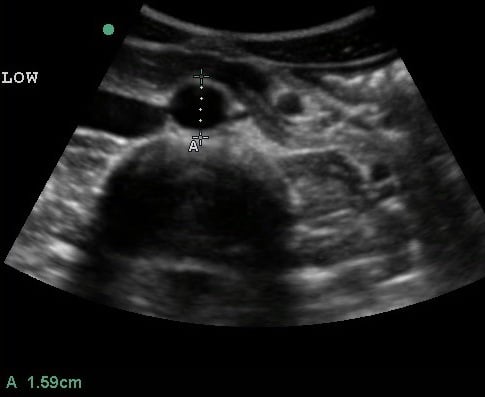

- Mid measurements should be obtained below the SMA branch point.

- Figure 4. Transverse view of the mid aorta

- Distal measurements should be obtained above the bifurcation.

- Figure 5. Transverse view of the distal aorta